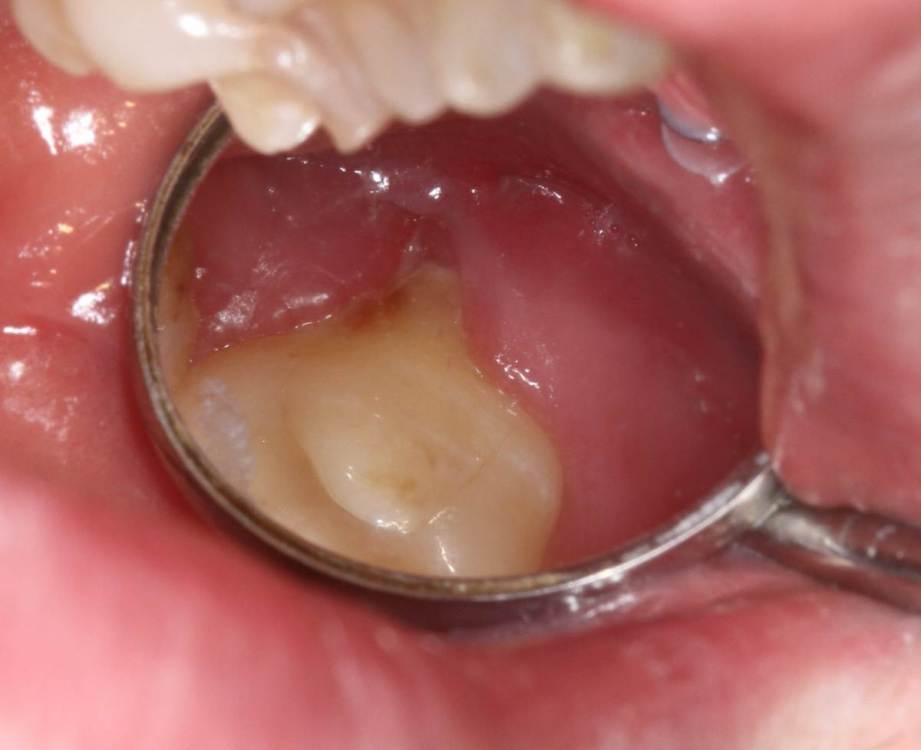

Kolchanov Опубликовано 19 августа, 2023 Поделиться Опубликовано 19 августа, 2023 Есть вот такой зуб 26. На дистальном корне рецессия, парадонтальный карман и дефект на корне явно не кариозного происхождения. Может кто покрутить КТ и сказать свои мысли по поводу процесса. https://drive.google.com/drive/folders/1B2huzkpPolt4XsAAIdYJuWwHHcJvr7iK?usp=drive_link Меня смущает, что, похоже, и на 28 (27 удалён) есть изменения и костная ткань тоже выглядит как-то подозрительно. Ссылка на комментарий